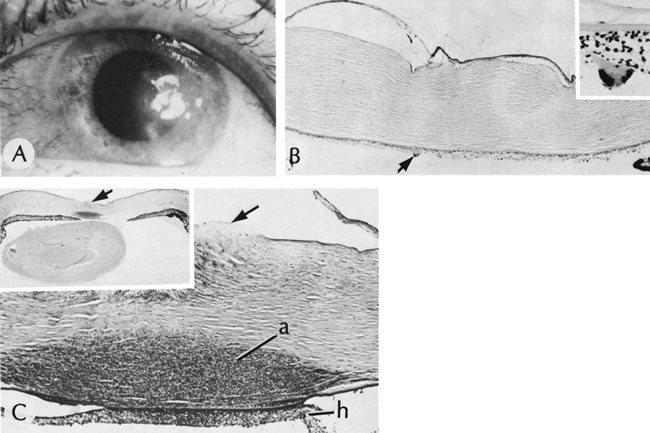

Herpes simplex is the most common cause of viral central corneal ulcers in the United States.120 The initial clinical sign may be a cutaneous vesicular rash (Fig. 17) or a corneal epithelial dendrite (Fig. 18). The infection progresses through corneal stromal inflammation (metaherpetic phase) to culminate in central ulceration. The initial epithelial defect is caused by replication of herpes simplex virions in the epithelial cells; the cytopathologic effect of the infection leads to epithelial cell death (rose bengal–positive) and ulceration. The infection is self-limited to an 8- to 10-day course unless shortened by debridement or antiviral therapy. The recurrence rate of initial dendritic infection by herpes simplex (25%) is not influenced by the type of treatment used. Most of the significant complications, such as corneal ulceration (Fig. 19), of herpetic keratitis are related to its tendency to initiate a delayed hypersensitivity type IV reaction, rather than the result of direct infection of the stroma.

By light microscopy, eosinophilic intranuclear inclusions are characteristic of herpes simplex viral infections and represent the result of viral replication (Cowdri type A inclusions).121 Hypersensitivity type IV reactions in the stroma are characterized by lymphocytic and plasmacytic infiltrates. Intranuclear inclusions are relatively rare and are not found in most specimens. Viral particles occasionally can be found in multinucleated giant cells or within the stroma, especially in keratocytes (Figs. 20 and 21).

Fig. 21. Herpes simplex. A. Clinical appearance of bullous keratopathy. B. Chronic condition shows development of bullous keratopathy. The anterior chamber inflammatory reaction contains multinucleated inflammatory giant cells (arrow), shown under high magnification in inset. C. Ulcerated bullous keratopathy (arrows). A corneal abscess (a) and hypopyon (h) are present. Note (inset) the subluxation of the lens to left, caused by the loss of zonula-lens attachments on the right, resulting in a “blunted” appearance of the right side of the lens. (Courtesy of SEI Photoarchives.)